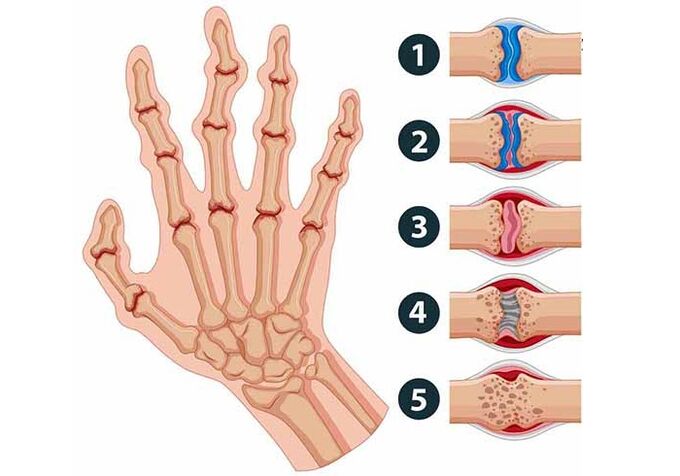

- Artrite reumatóide. Esta doença se manifesta de forma crônica; afeta pequenas articulações, mas em estado muito avançado pode se espalhar para as grandes, bem como para órgãos internos. Eles incham e ficam vermelhos e quentes. Simplesmente cerrar o punho já não é tão fácil como antes, porque o desconforto é muito forte. Muitas vezes afeta ambas as mãos ao mesmo tempo. A peculiaridade desta doença é que os dedos doem de manhã e de madrugada.

- Osteoartrite. Esta doença começa a alterar a forma das articulações, tornam-se mais espessas e limitam os movimentos. As mulheres mais velhas são mais propensas a esta doença. As razões para o desenvolvimento da osteoartrite: hereditariedade, aumento do estresse e muitos outros fatores. Os sintomas da doença geralmente são facilmente perceptíveis: dor, deformação dos dedos em formato de fuso.

- Deformidade articular.

Se houver dor nas articulações ao dobrar os dedos, você não deve esperar uma solução para o problema em si. Ao não consultar o médico a tempo, a pessoa desenvolve a doença, que traz consequências muito graves. Muitas vezes a mobilidade dos dedos é reduzida e, no futuro, pode surgir um problema como a inflexibilidade absoluta do dedo. Tais consequências às vezes levam uma pessoa a ficar com deficiência.